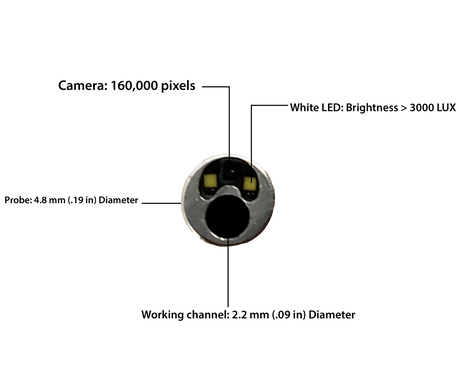

Replaceable Probe Camera for VE-8150 Veterinary Endoscope